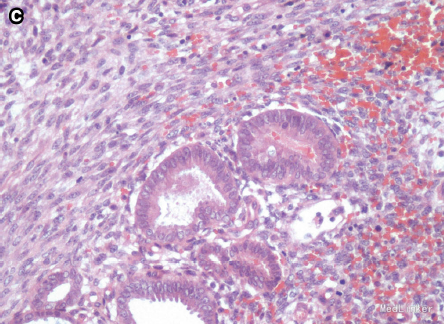

初步诊断为宫颈息肉 全麻下行肿物切除术,并将肿块基底部广泛切除 肉眼观为90*50*35mm带蒂肿块,有囊性部分和出血部分 病理提示为宫颈粘膜息肉,有子宫内膜基质和少数的内膜腺体

这个病例主要是提出来鉴别一下宫颈息肉和子宫内膜异位症,临床症状后者有周期性的出血比较重要,但是只从临床症状或者外观上还是不确定的,最好还是手术切除病灶做活检。